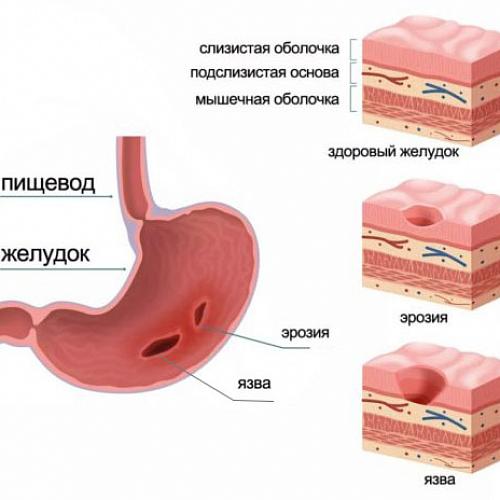

Информация и фотографии о хроническом гастрите и дуодените